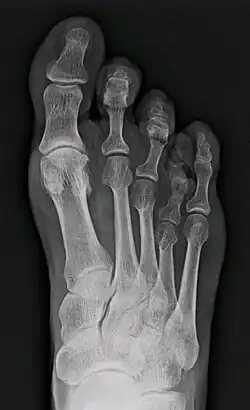

X-ray of congenital brachymetatarsia involving fourth metatarsal bone

Brachymetatarsia is a rare malformation that causes one or more toes to be abnormally short. The condition is characterized by a metatarsal arch shortness of more than 5 mm. The condition is more common in females, and the incidence reported in the literature ranges from 0.02% to 0.05%. Brachymetatarsia appears to be the result of epiphyseal plate retardation or premature closure. The etiology may be congenital and idiopathic, posttraumatic, postinfection, iatrogenic, or secondary to a systemic disease such as cancer, sickle cell disease, pseudohyperparathyroidism, Turner's syndrome, Down syndrome, Apert syndrome, athyroidism, or osteodystrophy.[2]

It most frequently involves the fourth metatarsal. If it involves the first metatarsal, the condition is known as Morton's syndrome. Treatment is via a number of differing surgical procedures.[3]